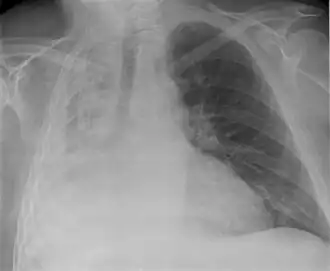

Raio X de atelectasia do pulmão direito.

Atelectasia (do grego ἀτελής, "incompleto" + ἔκτασις, "extensão") ou colapso pulmonar é o colapso de um segmento do pulmão alterando a relação ventilação/perfusão. Geralmente ocorre quando a via respiratória está bloqueada e as áreas não colapsadas costumam tentar compensar aumentando a oxigenação.[1]